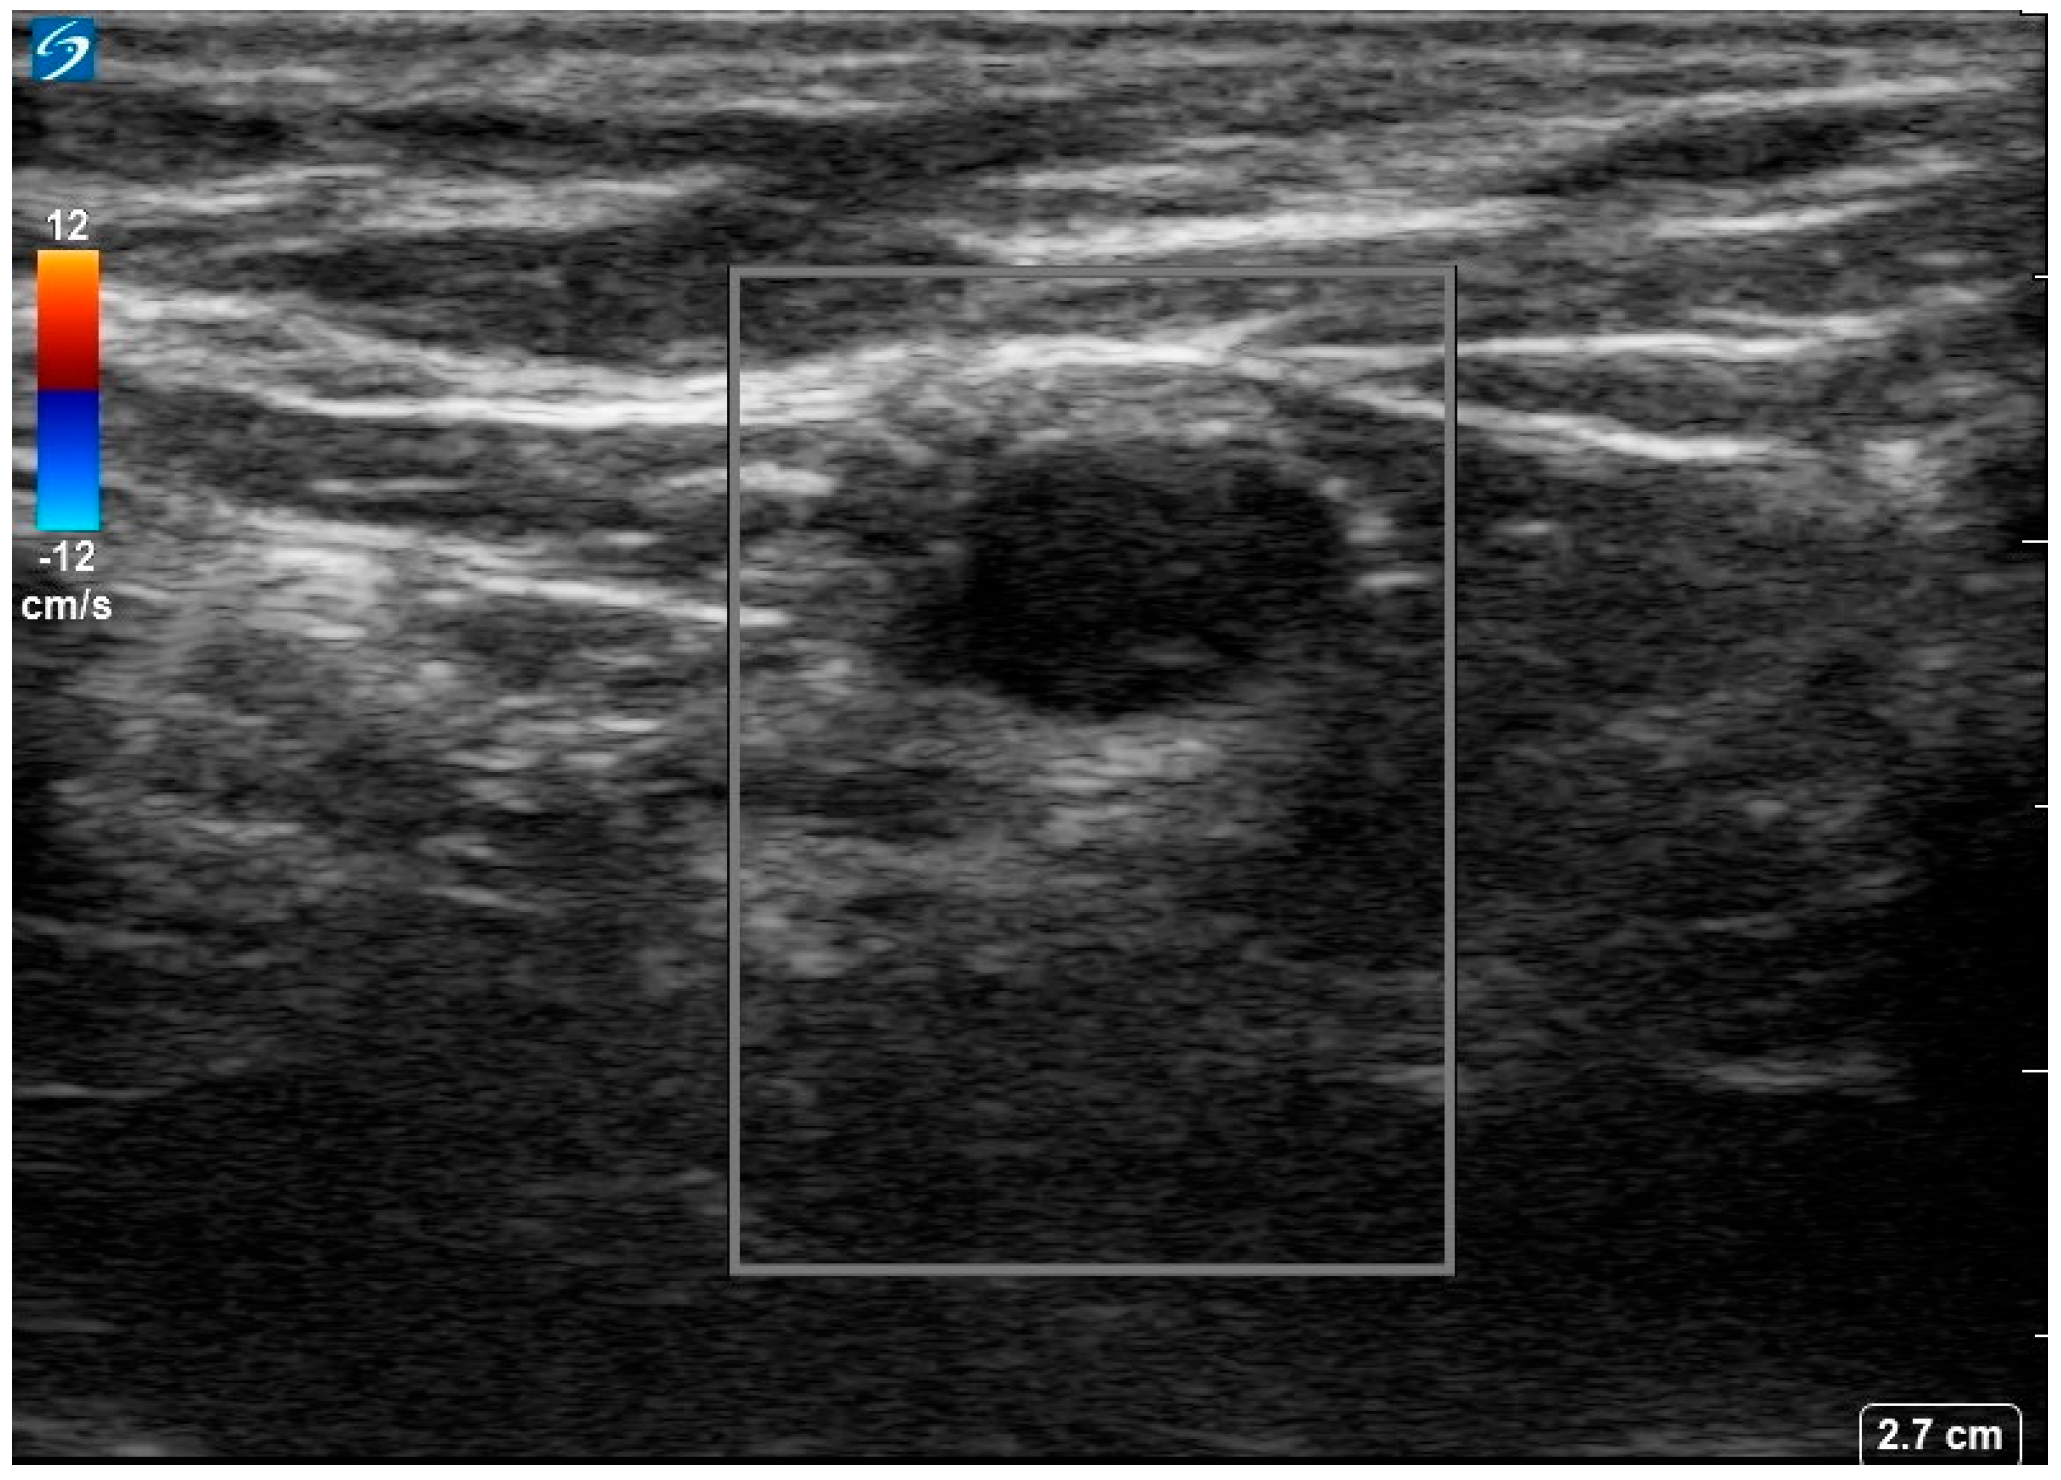

She was diagnosed with seronegative opsoclonus-myoclonus ataxia syndrome of paraneoplastic origin. Given suboptimal response to IVIG, she was started on 1 g IV methylprednisolone for 5 days. An ultrasound of the left axilla identified a 0.9 × 0.6 cm hypoechoic node with notable loss of the normal fatty hilum and reniform shape, irregular margins and prominent peripheral feeding vessels (Figure 2.

Figure 2.

Ultrasound image of the 18−FDG avid left axillary lymph node. Image shows a 0.9 × 0.6 × 0.7 cm markedly hypoechoic lesion with loss of normal fatty hilum, reniform shape, and irregular margins with prominent peripheral feeding vessels.